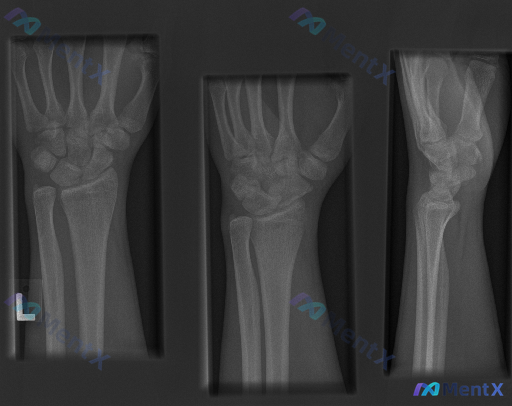

大家好,今天我们来讨论一份左侧腕部外伤后的X光片资料。先给大家看一下三个体位的影像学观察结果: 1. 放射影像-手腕处X光片-正位 (AP View) 骨骼完整性: 桡骨远端: 桡骨远端干骺端见明显骨折线,皮质连续性中断,呈现典型的背侧移位(Colles骨折特征),伴有明显的背侧成角和嵌插表现。桡骨...

整理到一份左前臂及腕部侧位X光片的影像资料,先和大家同步客观所见的线索: 1. 骨骼方面:桡骨远端背侧和掌侧皮质有连续性中断,可见骨折线涉及关节面,断端有背侧移位、背侧成角的表现,局部有粉碎或压缩改变;尺骨远端(尺骨茎突)处也可见透亮线。 2. 关节方面:桡腕关节的对应关系有改变,随桡骨移位出现背侧...